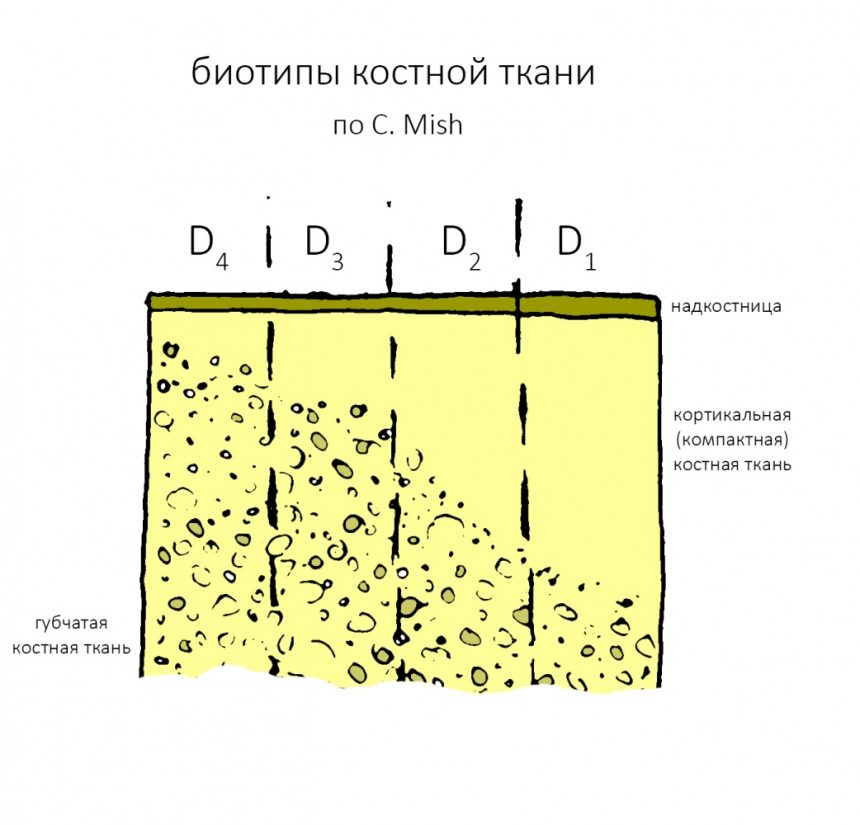

Соотношение внешней кортикальной и внутренней губчатой части челюстной кости определяет ее биотип.

В этой статье я уже рассказывал про биотипы костной ткани и том, почему это важно при планировании имплантации. Вот картинка, поясняющая, что такое биотипы, и в чём между ними разница:

Зная биотипы, удельное содержание клеточных элементов костной ткани, роль межклеточного вещества и то, как всё это влияет на регенераторные процессы, мы можем сделать интересные выводы:

- Биотипы D1 и D2 — наиболее сложные для имплантации и остеопластики, поскольку имеют выраженную кортикальную пластинку, почти не имеющую клеточных элементов, необходимых для регенерации. Это противоречит общепринятым представлениям, но именно так оно и есть. Смиритесь и отправляйтесь учить гистологию.